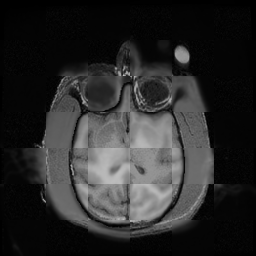

For each of the 10 subjects, we show checkerboard slices in each direction (1) before registration, first row; (2) after rigid->scaleversor->affine registration, second row; and (3) after BSpline registration, third row.

Gucci